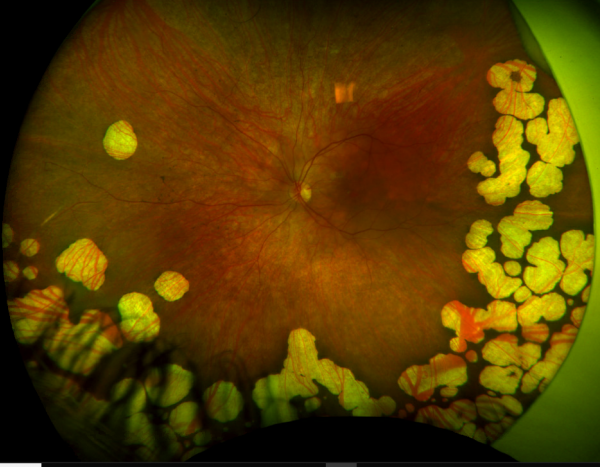

Gyrate Atrophy of the choroida and the retina is a rare autosomal recessive retinal dystrophy characterized by progressive chorioretinal degeneration, early cataract formation and myopia. It is caused by a deficiency in the enzyme ornithine aminotransferase (OAT), which results in a 10- to 20-fold increase in plasma ornithine concentrations. Patients classically present in the first decade of life with nyctalopia, with fundus exam revealing characteristic circular patches of chorioretinal atrophy distributed in the peripheral fundus (Figure 1). As the disease progresses, the atrophic lesions coalesce and advance centripetally toward the posterior pole[1] (Figure 2), correlating with progressive loss of peripheral vision. Macular involvement occurs late in the disease.

Fundus examination early in the disease course shows bilateral patchy, sharply demarcated circular areas of chorioretinal atrophy with hyperpigmented margins in the mid to far periphery (Figure 1). [2] Typically, during the second decade of life, the peripheral atrophic lesions coalesce and spread toward the posterior pole, forming a confluent lesion with a scalloped border at the junction of healthy and diseased retinal pigment epithelium (Figure 2). The remaining healthy RPE in uninvolved areas is hyperpigmented, distinguishing this disease from choroideremia.

Fundus Photography

Serial fundus photography, especially wide field fundus photography, is useful in monitoring progression of disease. In a study of two related patients with an unrestricted diet and photos taken 24 months apart, younger age and smaller lesion sizes at baseline were associated with a significantly faster rate of chorioretinal degeneration. [30]